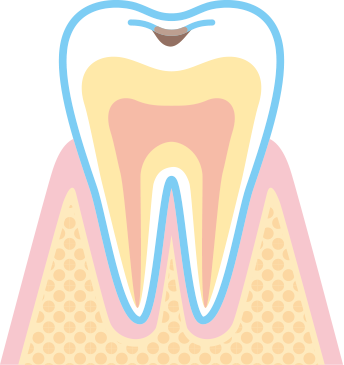

穴が歯の表面のエナメル質部分のみにできた状態です。

痛みはありませんがレジン(歯と同色の樹脂)やシーラント(患部消毒後の溝埋める)などの治療が必要です。